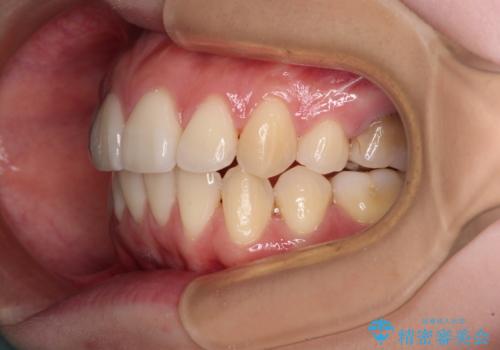

後戻りをインビザラインでスッキリした口元に

- 高校生の時に矯正治療を行ったものの、後取りをしてしまったとのことで来院された患者様です。

マウスピースでもワイヤー矯正でも対応可能でしたが、再度ワイヤーは装着したくないとのことでインビザラインにて矯正治療を行うこととしました。

舌の突出癖が原因で後戻りをしたため、舌のトレーニングをしっかりと行っていただき、口元の突出感を改善することができました。

インビザラインの装着時間が守れず、1年強で終わる予定でしたが、4年間を要することとなりました。